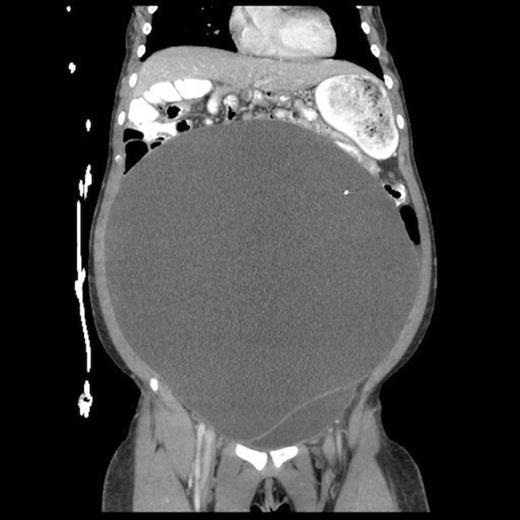

Post-operative abdominal CT demonstrating complete resolution of the fluid compartment

The patient underwent laparoscopic cyst drainage with removal of the cyst wall. A total of 12.7L of fluid was drained. Culture results and routine labs were all negative. A post-operative CT demonstrated complete resolution of the fluid compartment (Fig. 4). The VP shunt catheter was initially left in the abdominal cavity. One month later, however, she developed significant recurrence of fluid collection (Fig. 5) and lethargy from malfunction of the VP shunt. The recurrent fluid was drained under ultrasound guidance, and her abdominal shunt catheter was removed. A new shunt catheter was placed in the right atrium, and the patient made a full recovery without any further complications.